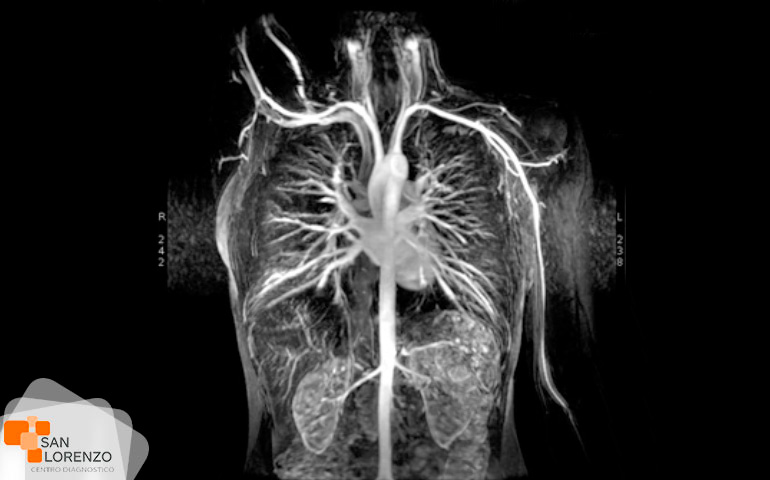

Algunos de los exámenes relacionados con medios de contraste son: Angiotac, Urotac, TAC de abdomen y pelvis, TAC de cerebro en lo que se solicite contraste, y todas aquellas Resonancias magnéticas contrastadas.

Todos los exámenes de RM, TAC que requieran contraste tal como los mencionados anteriormente: Angiotac, Urotac, TAC de abdomen y pelvis, TAC de cerebro en lo que se solicite contraste y todas aquellas Resonancias magnéticas contrastadas.